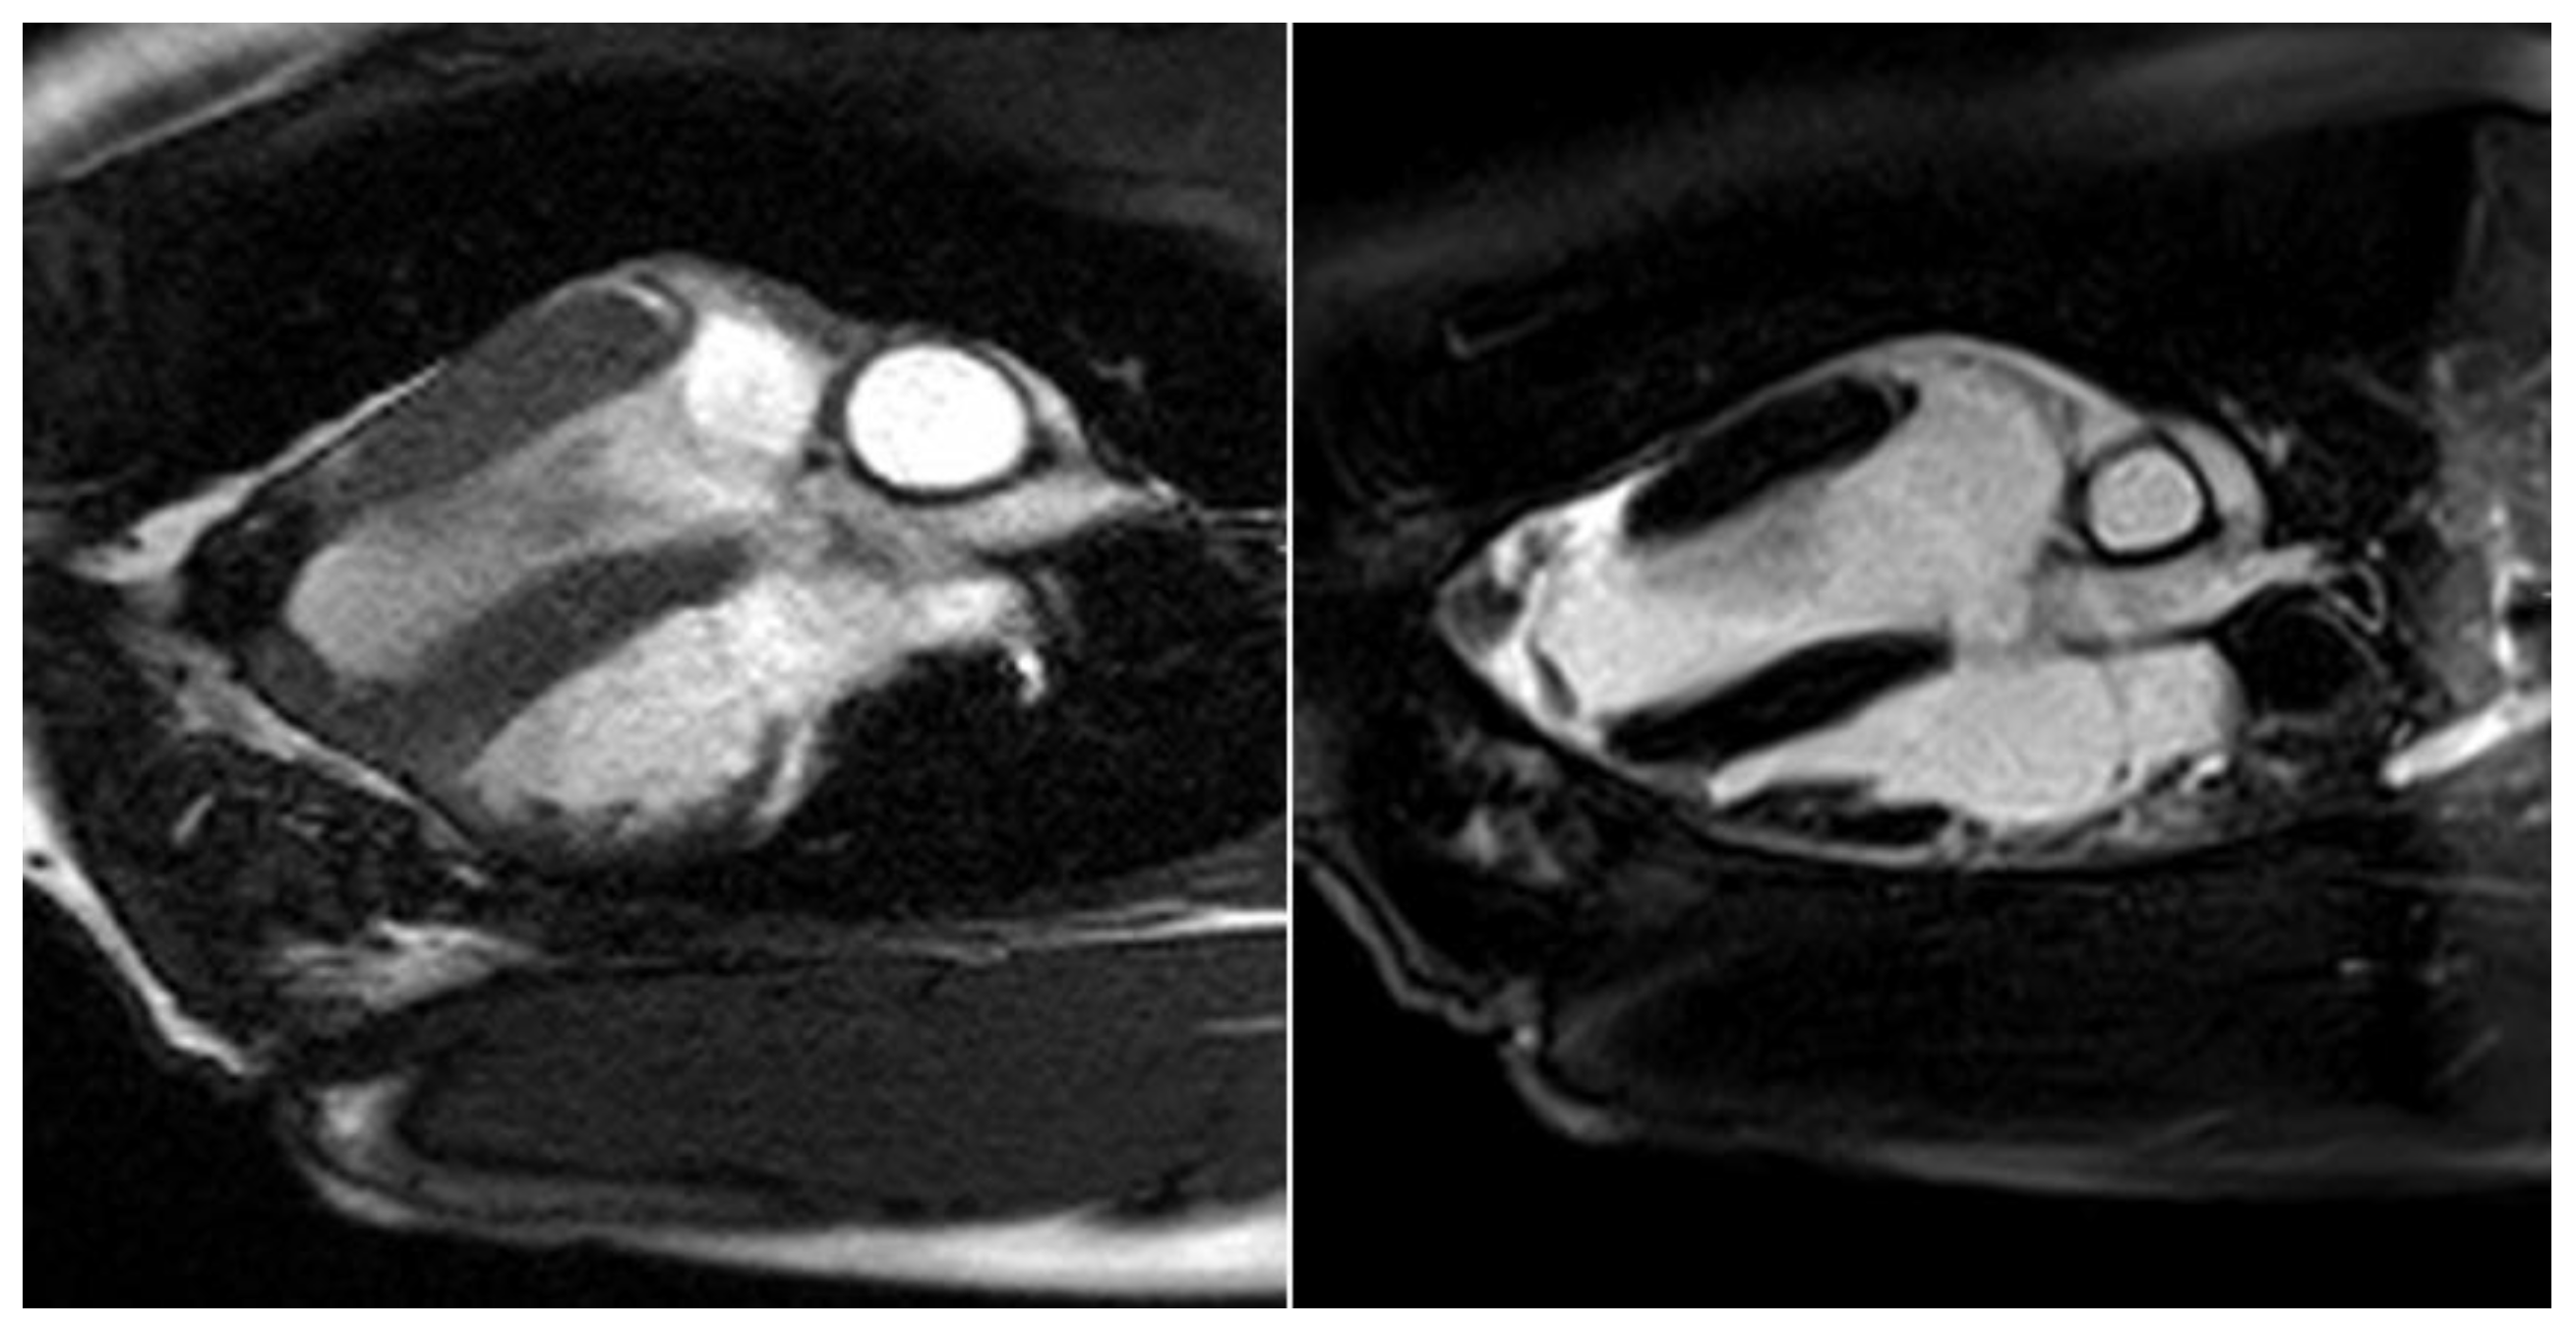

The border zone between the myocardium and the stomach patch showed an intense late enhancement of the contrast agent as an expression of the adjacent stabilizing fibrotic remodeling processes in these animals (see Figure 8).

Figure 8.

Cardio MRI six months following myocardial reconstruction with a vascularized stomach patch, stabilized with degradable magnesium alloy scaffolds. Delayed enhancement imaging. Left: cine SSFP. Right: four-chamber view with signs of distinct late enhancement in the left ventricular, apical zone, indicating cicatricial remodeling.

However, the left ventricular ejection fraction was still reduced (50%), and the region of the stomach patch was akinetic. There was a paradoxical systolic outward movement of the affected area and a reduction of left ventricular ejection fraction of 15%–18% in the animals with an aneurysm. The aneurysms had a total volume of 12–18 mL. The delayed enhancement of the contrast agent was seen in these animals, mainly in the border zone between the native myocardium and the stomach tissue.